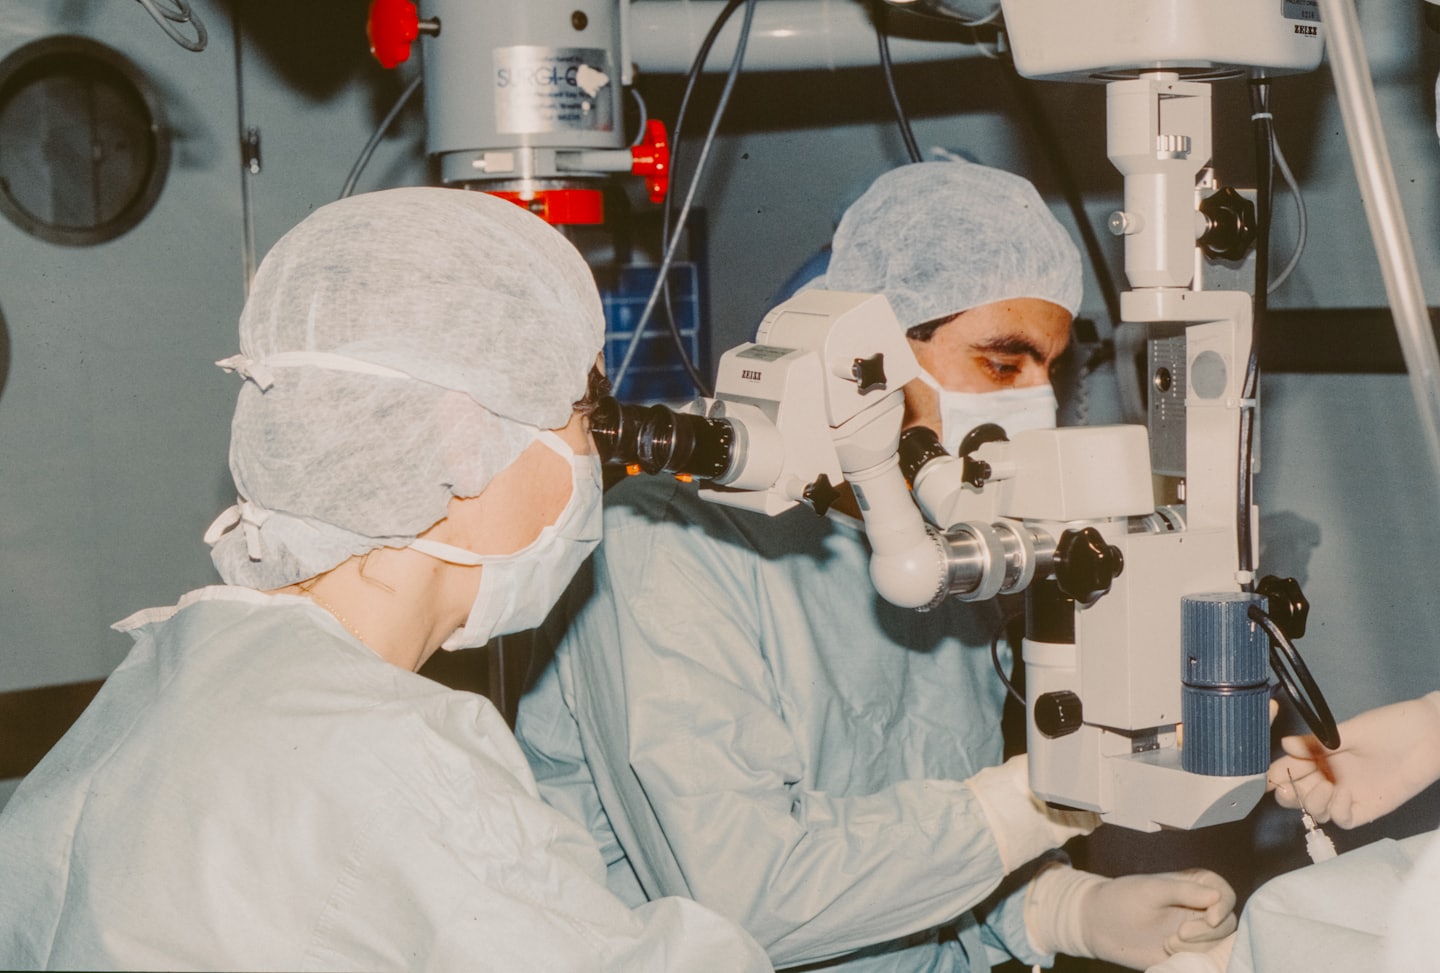

Aqui apresentamos fotos exclusivas que capturam momentos e experiências do curso Elite HPS.

Explore nossa galeria que captura a excelência, inovação e momentos marcantes do curso Elite HPS.